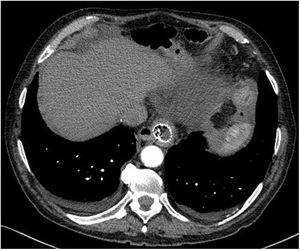

Sin embargo, a las 24 h reingresa por hematemesis con angio-TC normal (fig. 1), realizándose endoscopia que controla la hemorragia mediante clips sin visualizar adecuadamente la endoprótesis. Mediante nueva endoscopia a las 8h, se retira esta y se verifica la hemostasia, aparentemente adecuada. Cinco días después presenta nueva hemorragia con inestabilización, no consiguiéndose control endoscópico, por lo que se decide intervención quirúrgica urgente vía abierta con sospecha de fístula aortoesofágica. La revisión de la angio-TC, previa a la retirada de la endoprótesis, apoya el diagnóstico al objetivar la proximidad de la porción proximal de la misma con la aorta, tal y como se muestra en la reconstrucción 3D (fig. 2). Durante la cirugía, se confirma la fístula, que se repara con sutura aórtica directa. Para su visualización, es preciso deshacer la anastomosis esófago-yeyunal, realizándose esofagectomía, esofagostomía cervical y yeyunostomía de alimentación.